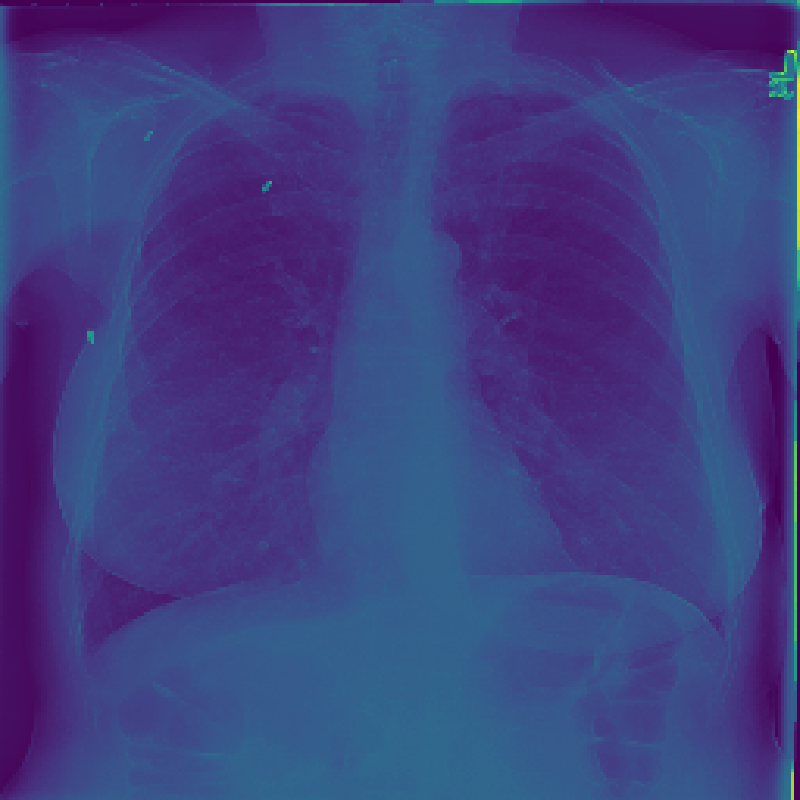

Figure 3: The feature map visualization of the GMSM and QCM modules. (a) Original image; (b) f1subscript𝑓1f_{1}italic_f start_POSTSUBSCRIPT 1 end_POSTSUBSCRIPT in Eq. 1; (c) f2subscript𝑓2f_{2}italic_f start_POSTSUBSCRIPT 2 end_POSTSUBSCRIPT in Eq. 1; (d) f3subscript𝑓3f_{3}italic_f start_POSTSUBSCRIPT 3 end_POSTSUBSCRIPT in Eq. 1; (e) Output of GMSM y𝑦yitalic_y; (f) Output of QCM; (g) Residual between y𝑦yitalic_y and QCM output.

3.2 Visualization of Feature Maps

In this section, we visualize the feature maps of the GMSM and QCM modules, as shown in Figure 3. From Figures 3 to 3, we observe that, during GMSM’s downsampling process, the earlier layers effectively capture the skeletal and organ contours in the X-ray image, while the later layers extract more abstract features. This observation suggests that GMSM progressively extracts key information in a coarse-to-fine manner. As shown in Figure 3, the output from the QCM module closely resembles the feature map of y𝑦yitalic_y in Figure 3. Additionally, the residual map in Figure 3 appears generally darker, indicating the QCM module’s effectiveness in compensating for quantization loss.